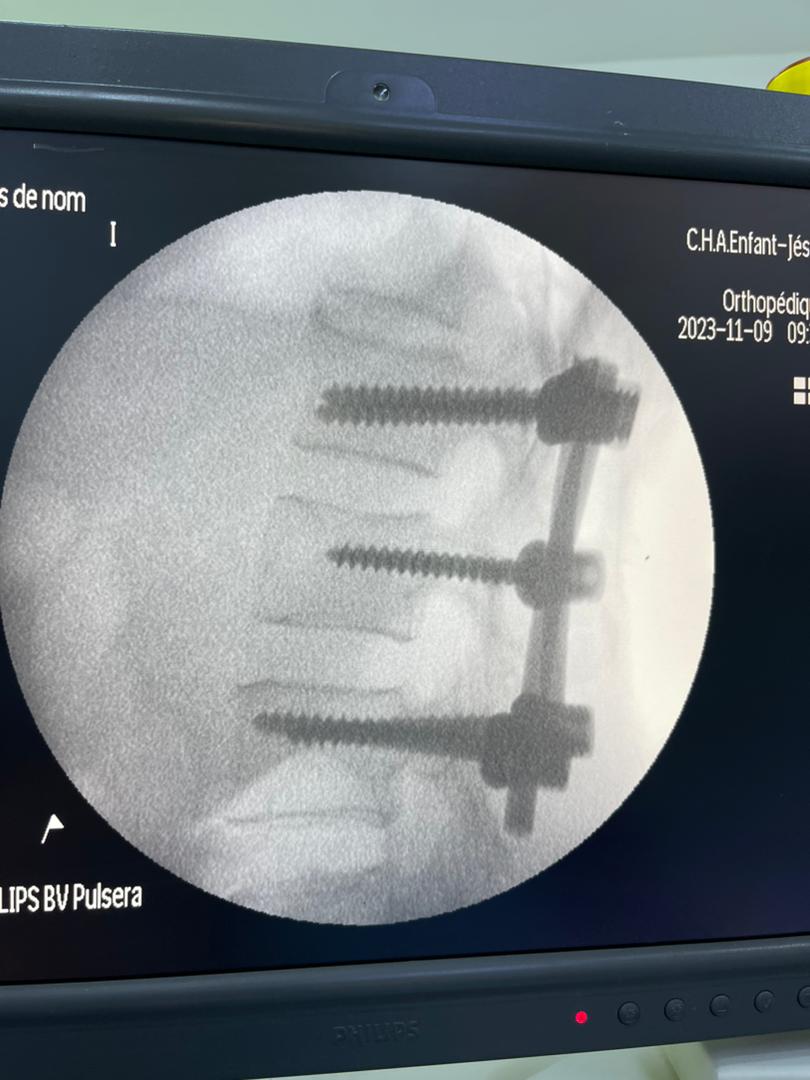

حيث قام الدكتور الشعيبي بتركيب جهاز إليزاروف، وهو جهاز خاص يستخدم لتصحيح العظام المشوهة أو المكسورة، على ركبة الطفلة، وبدأ بتحريك الركبة بشكل تدريجي ، حتى تم فرد الركبة بالكامل بعد شهر ونصف من العلاج دون الحاجة إلى جراحة تقليدية. وبعد ذلك، تم إزالة الجهاز، وبدأت الطفلة بالتأهيل الطبي والعلاج الطبيعي، حتى استعادت حركة الركبة وقدرتها على الانحناء والمشي بسهولة وثقة.